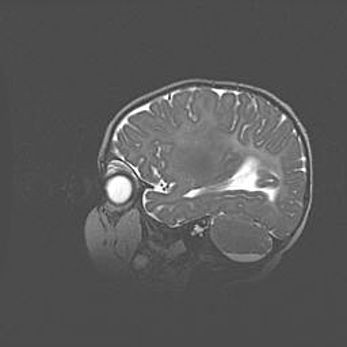

Мальформация Денди-Уокера. Киста задней черепной ямки.

Агенезия мозолистого тела.

Возраст: 2,5 месяца

Вес: 2420 г

Пол: женский

Окружность головы: 37 см

Срок гестации: 32 недели

Мальформация Денди—Уокера — редкий вид патологии ЦНС, представляющий собой врожденный порок развития каудального отдела ствола и червя мозжечка, ведущий к неполному раскрытию срединной (Мажанди) и латеральных (Лушка) апертур IV желудочка мозга. Для этогно синдрома характерна триада симптомов: гипотрофия червя мозжечка и/или полушарий мозжечка, кисты задней черепной ямки, гидроцефалия различной степени. В 70% случаев порок сочетается и с другими аномалиями головного мозга, в частности с агенезией мозолистого тела.